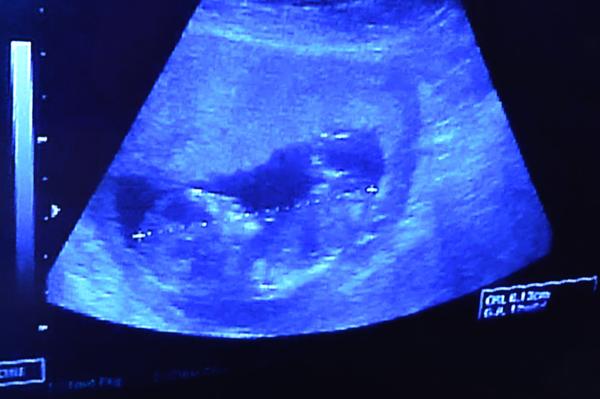

Dnes jsem byla po 4 týdnech na kontrole. Hlavička měřila 2,41cm (13+0) a tělíčko při prvním měření 6,13cm (13+0) a když měřil znova aby vytiskl fotečku tak jen 5,95cm (12+6) . Není to málo ? Všude se píše,že by měl mít tak 8cm

Přikládám foto z ultrazvuku před 4 týdny + dnešní + fota focené dnes mobilem z monitoru.